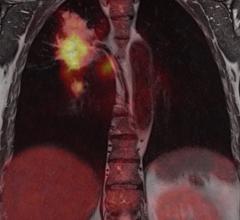

An emerging cancer therapy has colorectal tumors surrounded. Presenters at the 2016 Annual Meeting of the Society of Nuclear Medicine and Molecular Imaging (SNMMI) unveiled a novel radioimmunotherapy that combines a cancer-seeking antibody with potent radionuclide agents, resulting in complete remission of colorectal cancer in mouse models.